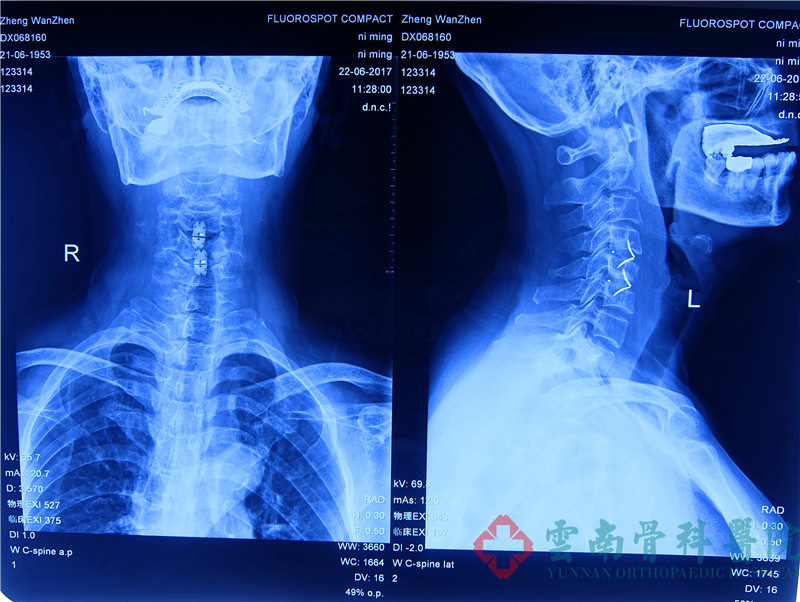

患者影像资料诊断:颈椎骨质增生严重、颈椎退行性改变严重

术后患者片子诊断显示融合效果很好